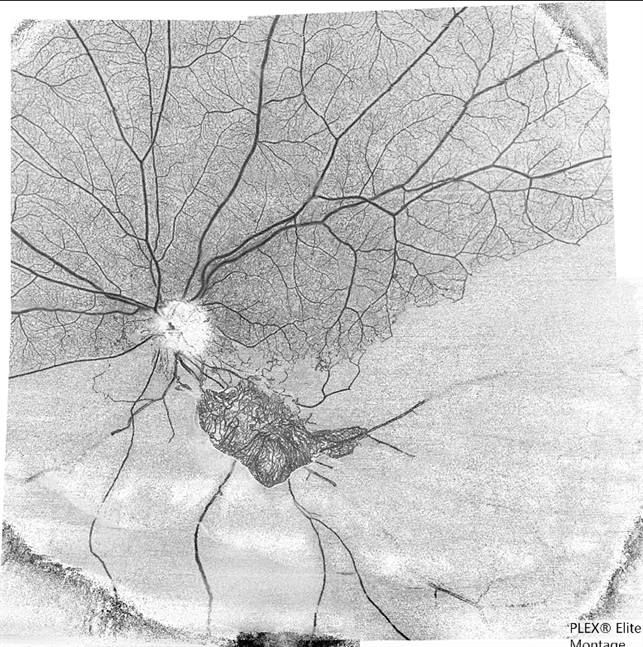

- hemi CRVO, neovascularization elsewhere (NVE)

- A 59-year-old man with DM for 18 years operated for mature cataract. Post op left eye had a visual acuity of 20/80. Wide field swept source OCTA revealed gross vessel wipe out in inferior hemi quadrant with branching out neovascular frond inferior to disc with terminal loops, The patient underwent Anti VEGF injection followed by OCTA guided sectoral retinal photocoagulation.Image J software used here to generate reverse image that sharply delineates the non perfusion area.